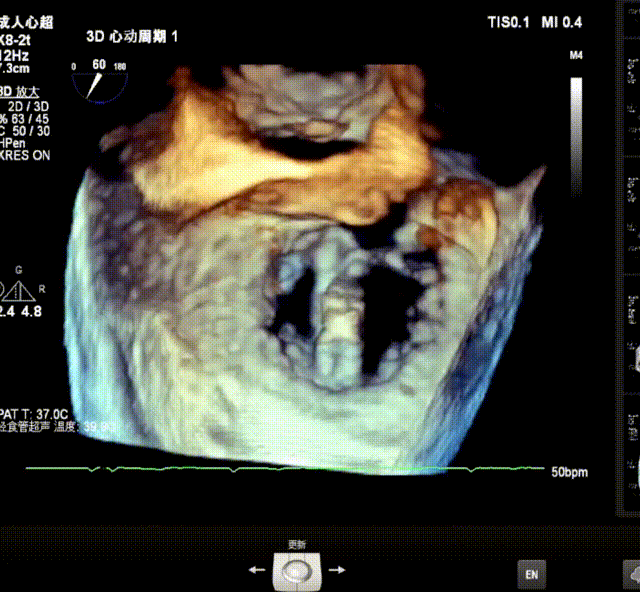

3D指示下调整瓣膜夹朝向病变区域P2偏P3区

确定瓣膜夹与病变区域垂直后,放下夹片,超声确认前叶后叶都夹合充分,3D检查瓣膜夹位置.

最终释放用多普勒超声评估返流程度,返流情况改善明显,仅存在极微小返流;无瓣口狭窄;肺静脉逆流情况消失,血流动力学显著改善;3D超声下,瓣膜组织桥稳定。术后即刻评估,术后反流消失(MR 0+),术后跨瓣压差2mmHg,手术成功。